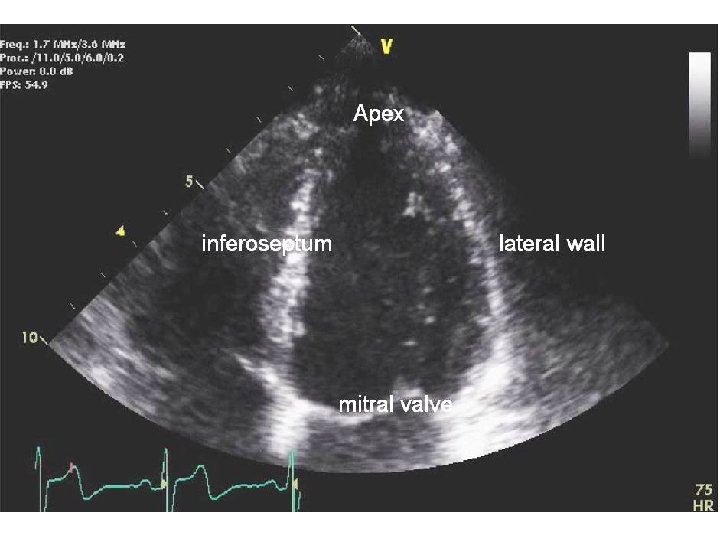

APICAL 4 CHAMBER VIEW